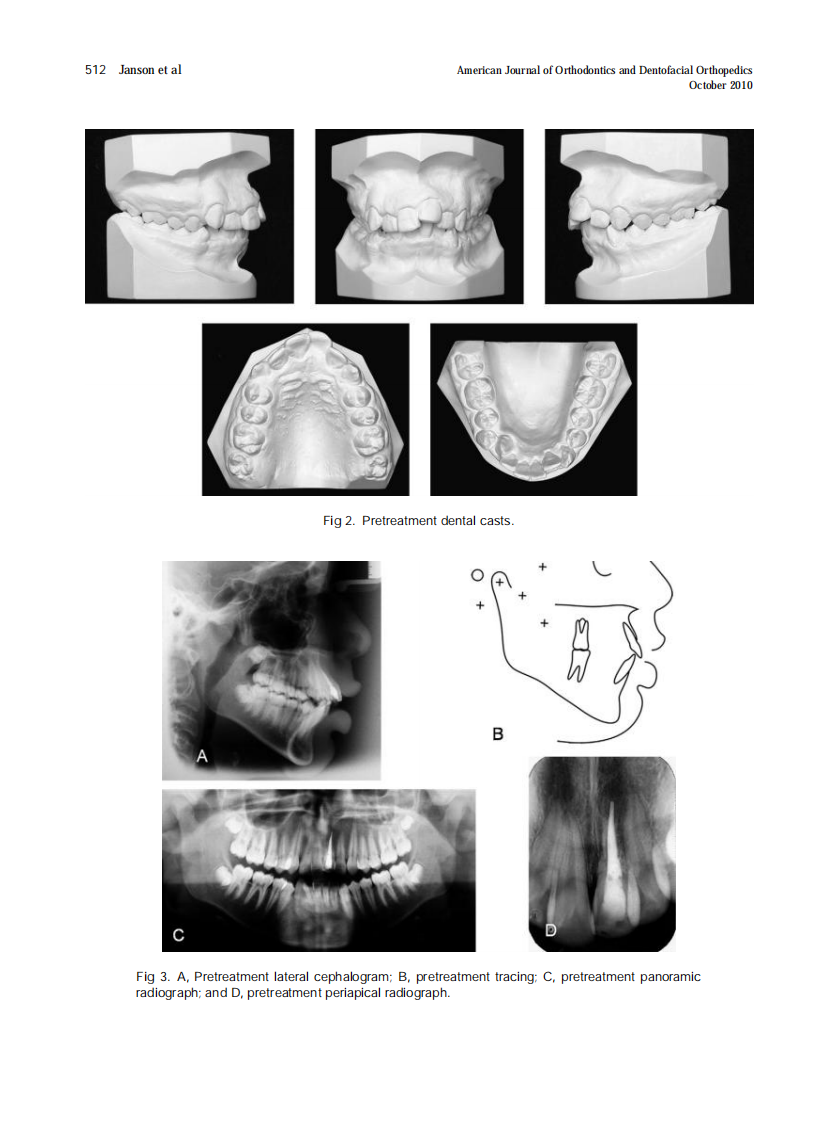

AJO-DO

2010_138_4_510_517.pdf